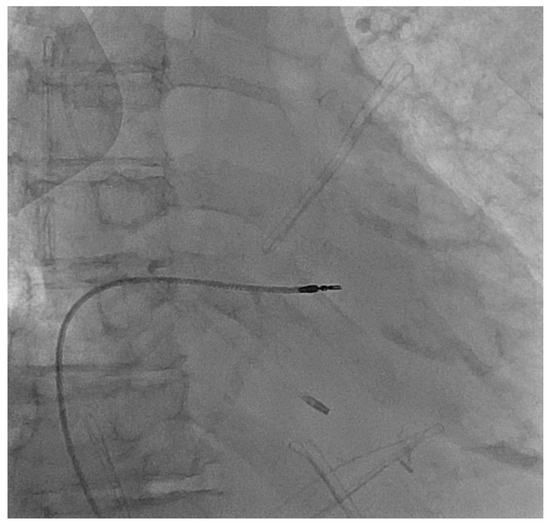

2. Case Presentation